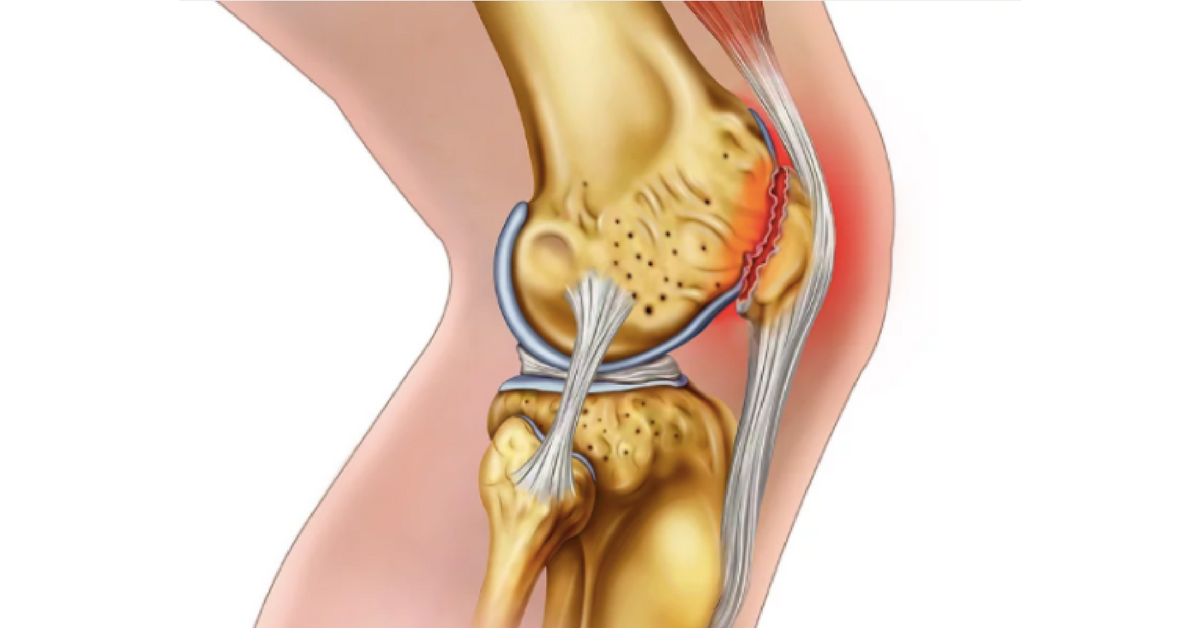

Our Advanced Knee Pain Program Helps Relieves or Eliminates:

•  Crunching & popping

•  Bone on bone

•  Tendonitis

•  Bursitis

•  Meniscus injury

•  Weakness & buckling

•  Cartilage damage

•  Arthritis